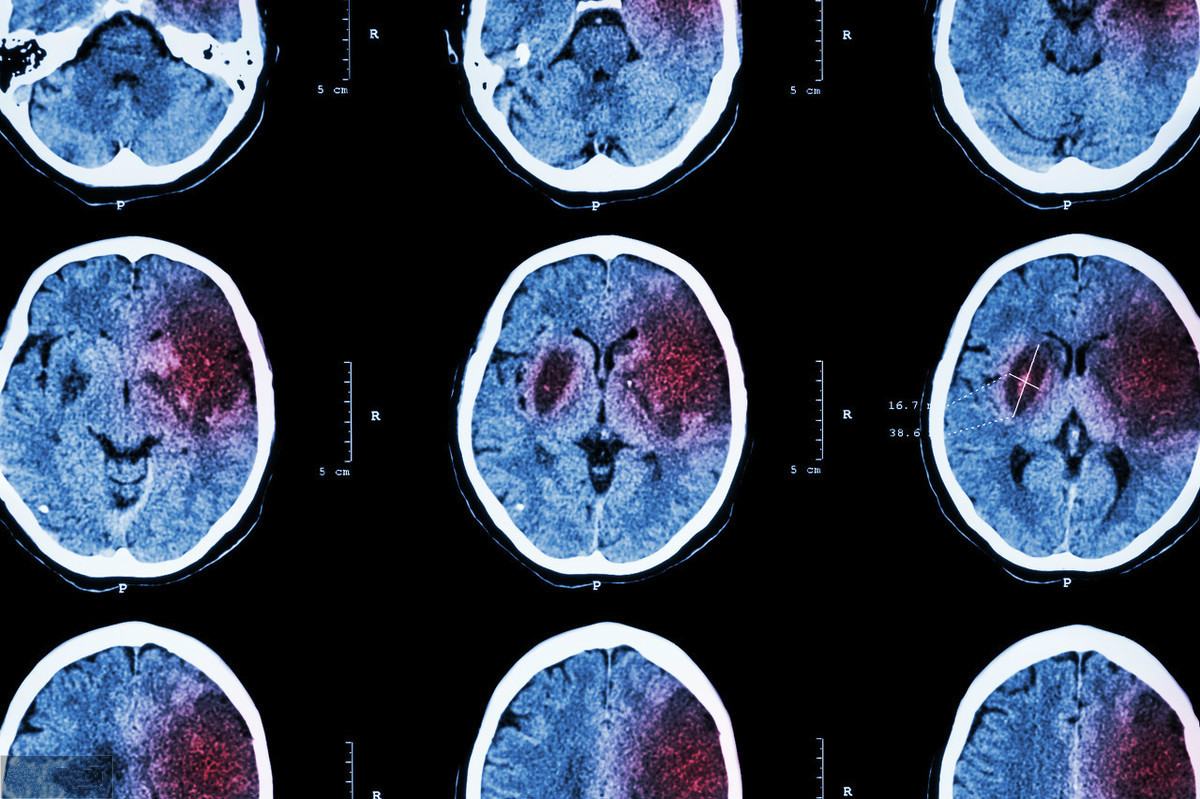

肌張力增高絕大部分見(jiàn)于上運(yùn)動(dòng)神經(jīng)元損傷而引起的疾病,例如腦出血、腦梗死、腦外傷、腦腫瘤、腦部的一氧化碳中毒、腦部的重金屬中毒、細(xì)菌性腦膜炎、病毒性腦膜炎等,肌張力增高臨床上是一種比較難以解決的疾病。肌張力高的治療方法包括保守治療和手術(shù)治療兩個(gè)方面。具體要選擇哪種治療方案,還是要根據(jù)具體的病因來(lái)確定。